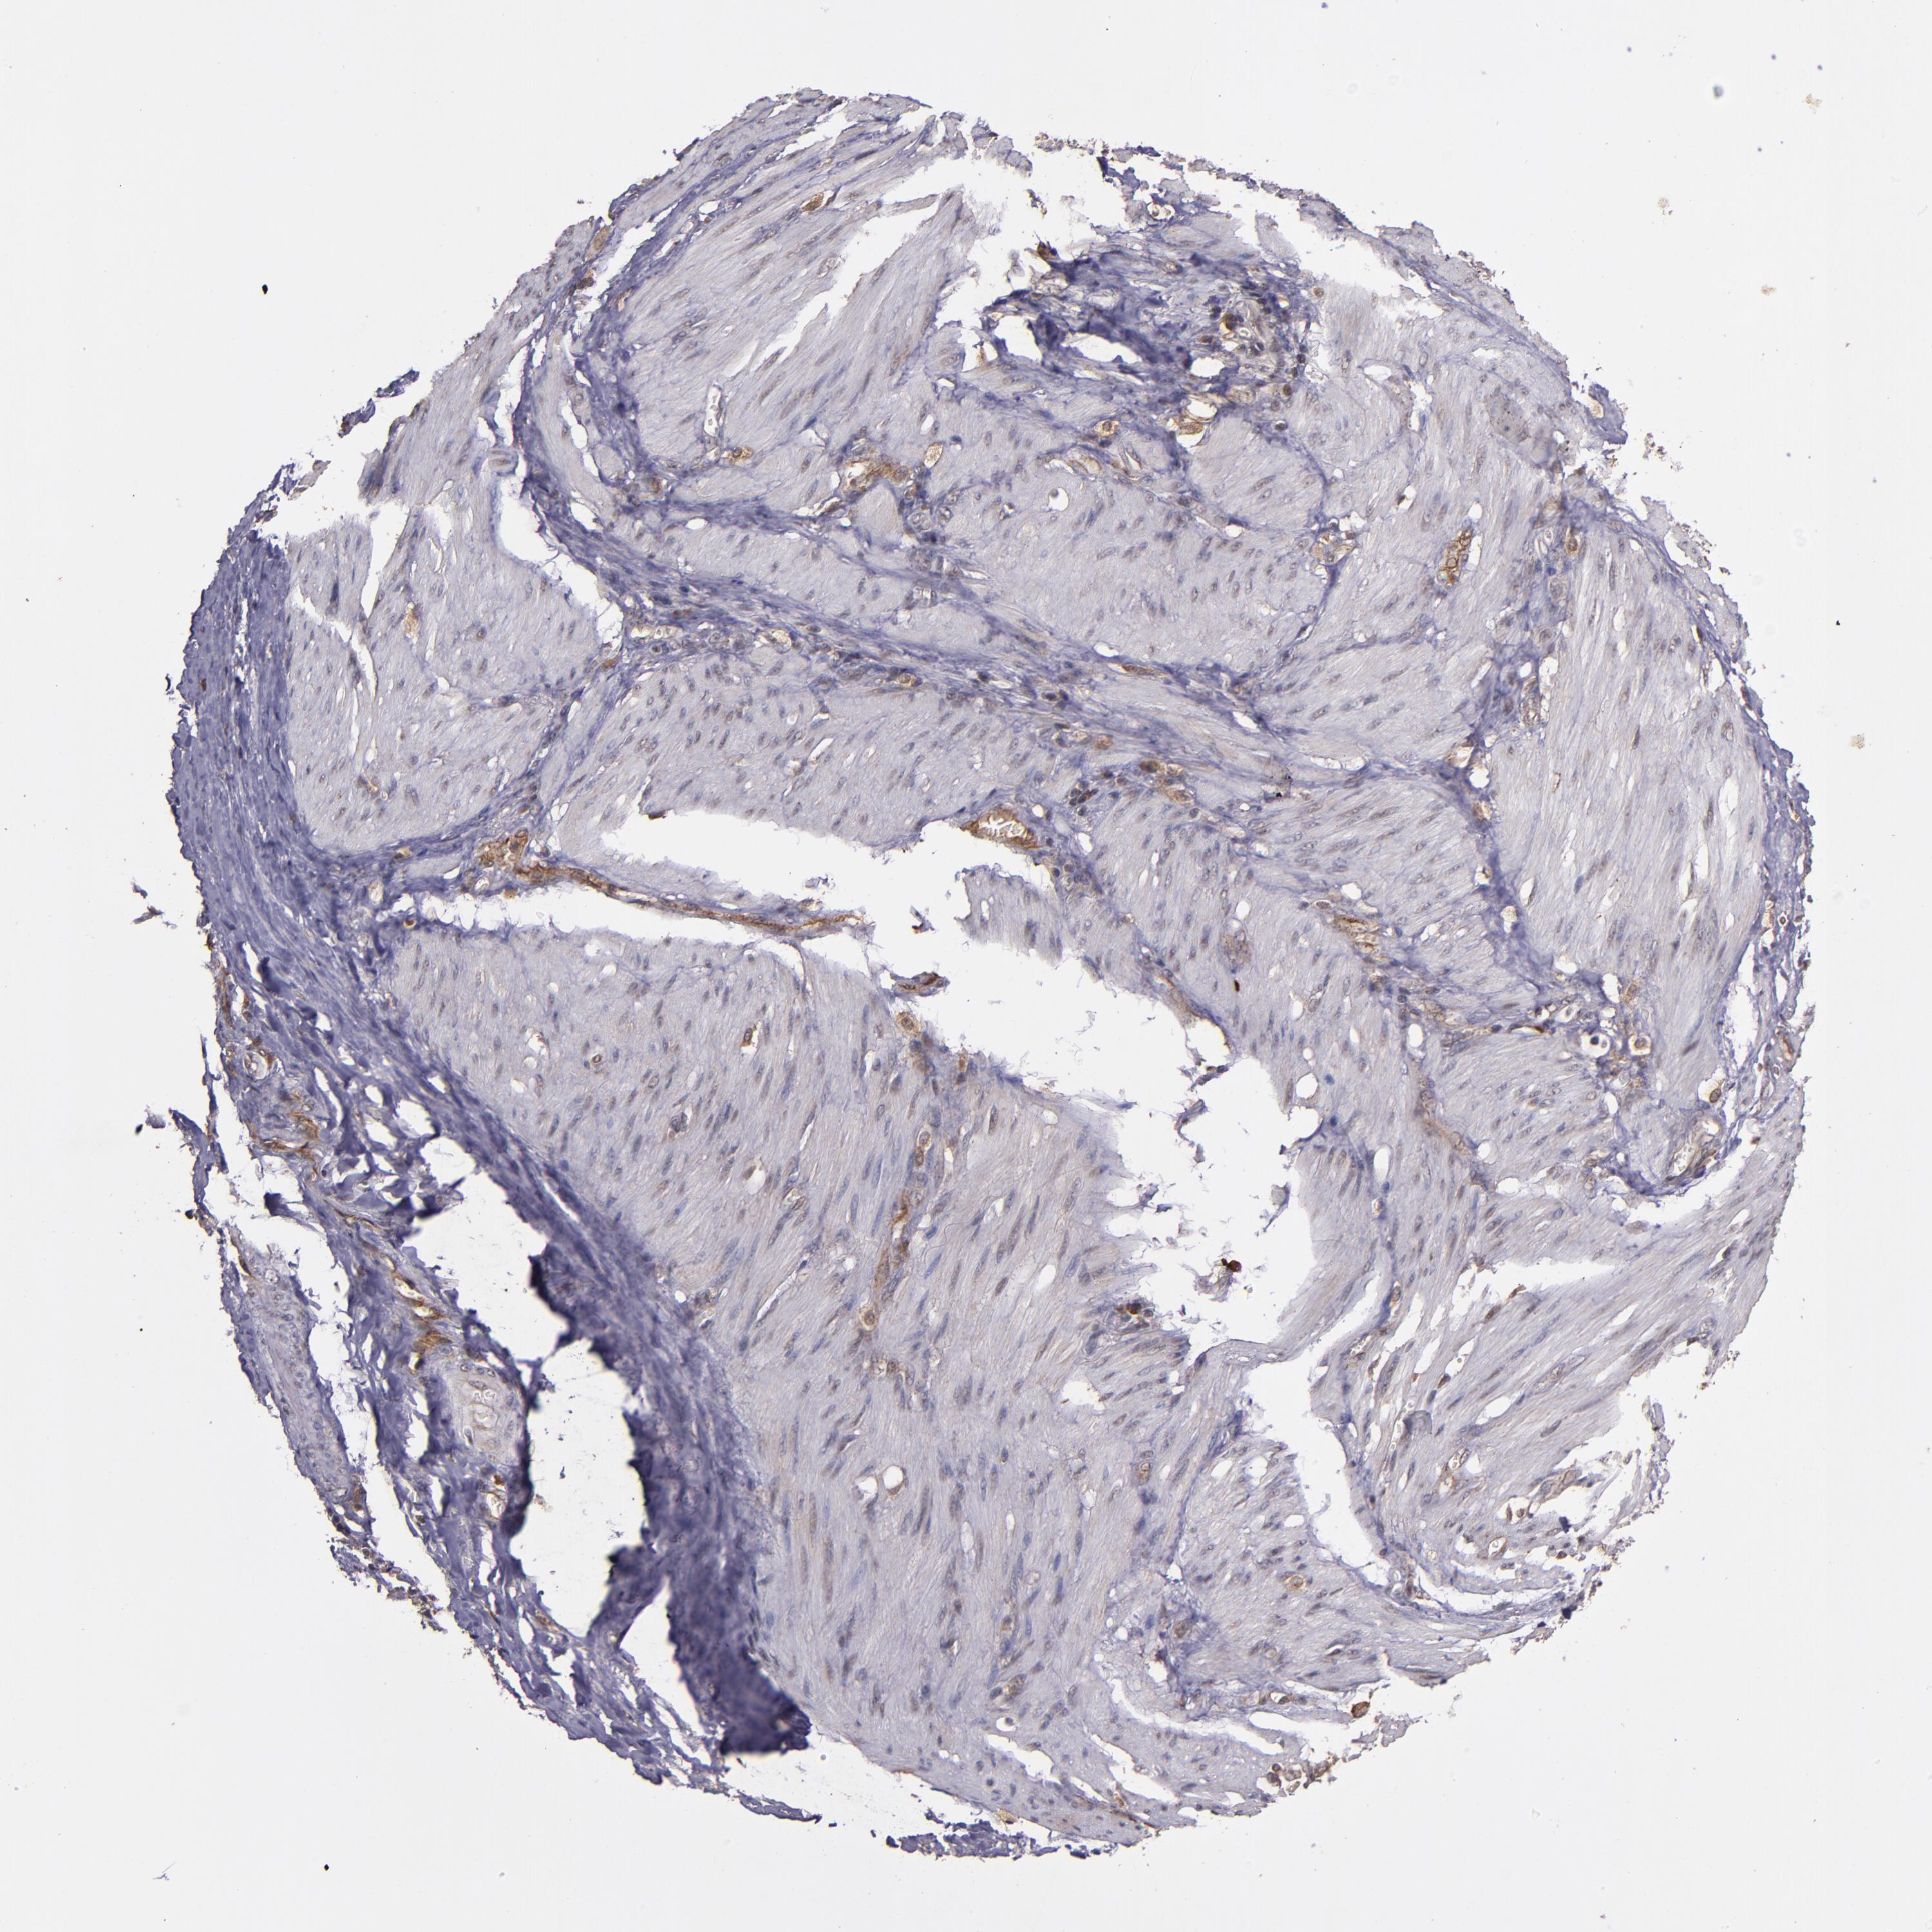

STOMACH CANCER - Protein expressioni

A mouse-over function shows sample information and annotation data. Click on an image to view it in a full screen mode. Samples can be filtered based on level of antibody staining by selecting one or several of the following categories: high, medium, low and not detected. The assay and annotation is described here.

Note that samples used for immunohistochemistry by the Human Protein Atlas do not correspond to samples in the TCGA dataset.

Antibody stainingi

Antibody staining in the annotated cell types in the current human tissue is reported as not detected, low, medium, or high, based on conventional immunohistochemistry profiling in selected tissues. This score is based on the combination of the staining intensity and fraction of stained cells.

Each image is clickable and will lead to virtual microscopy that enables deeper exploration of all samples and also displays staining intensity scores, fraction scores and subcellular localization as well as patient and tissue information for each sample.

Antibody HPA001620

Antibody HPA024184

Staining

High

Medium

Low

Not detected

Intensity

Strong

Moderate

Weak

Negative

Quantity

>75%

75%-25%

<25%

None

Location

Nuclear

Cytoplasmic/membranous

Cytoplasmic/membranous,nuclear

Adenocarcinoma, NOS